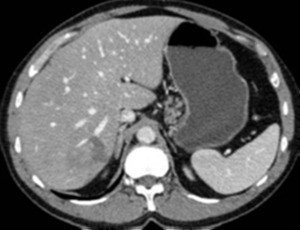

- Birinci və VI seqmentin hipertrofiyası (bu seqmentlərin bəzi venaları birbasa boş venaya açıldıqları üçün bu seqmentlərin funksiyaları saxlanılır, hətta hipertrofiyaya məruz qalır).

- Görüntüləmədə I seqment hipertrofiyası (yüksək şübhə əlaməti)

Baddi-Kiari sindromu böyük qaraciyər venalarının tıxanması nəticəsində meydana gələn venoz durğunluqdur, qaraciyər venaları ilə yanaşı aşağı boş venada da tıxanma ola bilir. Tromboz, fibroz, membran və infiltrasiya (şişlər, iltihab) ən çox rast gələn səbəbləridr. Erkən mərhələlərdə kəskin hepatit və kəskin qaraciyər yetməzliyi, xroniki mərhələdə sirroz və PH meydana gələ bilir. Diaqnozu üçün tomoqrafiya və kontrastlı angioqrafiya lazım gəlir, Qc venalarının trombotik tutulması diaqnozu təsdiqləyir. digər xarakterik əlaməti birinci seqmentin hipertrofiyasıdır. Erkən mərhələdə dekompressiya (cərrahi və stend) sirroz əmələ gəldikdə isə transplantasiya ön planda tutulur.

- Görüntüləmədə I seqment hipertrofiyası (yüksək şübhə əlaməti);

- Görüntüləmədə qaraciyər venalarının tıxanması, I seqment hipertrofiyası ola bilər (xroniki forma);